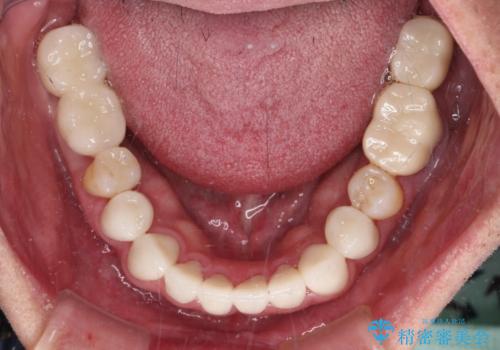

憧れの白い歯に 全顎セラミック治療

- 60歳を越え、黄ばんだ前歯をセラミッククラウンできれいな口元にしたいとのことで来院された患者様です。

診察したところ、前歯は反対咬合であり、その影響で抜歯が必要な奥歯があることが分かりました。

抜歯が必要な奥歯は、インプラント並びにブリッジにより補綴を行い、上下前歯は反対咬合を改善させるように補綴治療を行うこととしました。

健全な歯を削ってセラミッククラウンに置き換えることは、本来避けるべき治療と考えますが、今回は①患者様が60歳を越えていること、②要改善の咬合により抜歯が必要な奥歯があること、③反対咬合の前歯改善の手段としてセラミック治療が選択肢にあることなどから、全顎的なセラミック治療を行うこととしました。